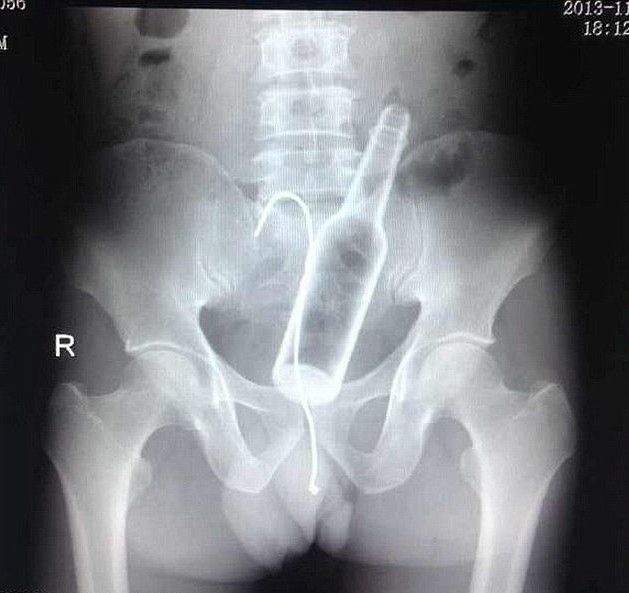

同じマンガで、アソコが痛いと主婦がやって来て、レントゲン撮ったら編み物に使うかぎ針が。なんで?と混乱する主婦…が、そう言えば学生の頃にオ〇二ーしててかぎ針使ってて抜けなくなり、そのうち出てくるとほっといて忘れてたって…。

10年は異物入れたまま、夫婦生活もしてたって…わからんかったんか?って話もあった。

「うわぁ」と思った数年後、テレビ見てたらその女がミスコンで優勝しててビックリした…って話をむかしマンガで読んだ。

ち●こ写っとるな